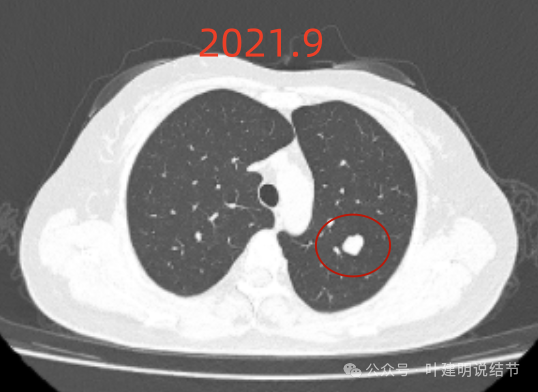

2021年9月,病灶相仿,但与邻近血管的距离似乎较最初的更靠近一点。